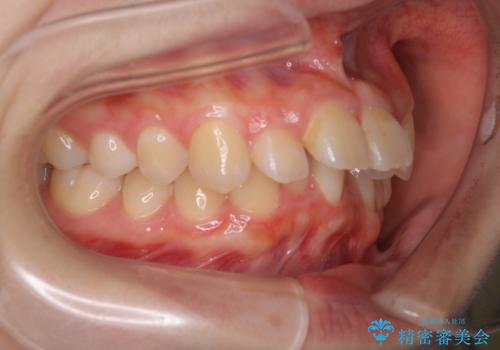

下顎前歯が1本欠損していることもあり、前突はある程度残ることを説明し、インビザラインにて治療を行いました。

今回は抜歯矯正ではなく歯列弓の拡大とIPR、遠心移動を行って配列することができました。

下顎前歯が1本少ないため、上下の正中は合いません。